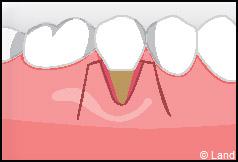

Les greffes de conjonctifs enfouis :

Destinées aux zones esthétiques, elles consistent à prélever la partie profonde du palais (site donneur).

Ce greffon est ensuite inséré sous la gencive au niveau de la récession (site receveur).